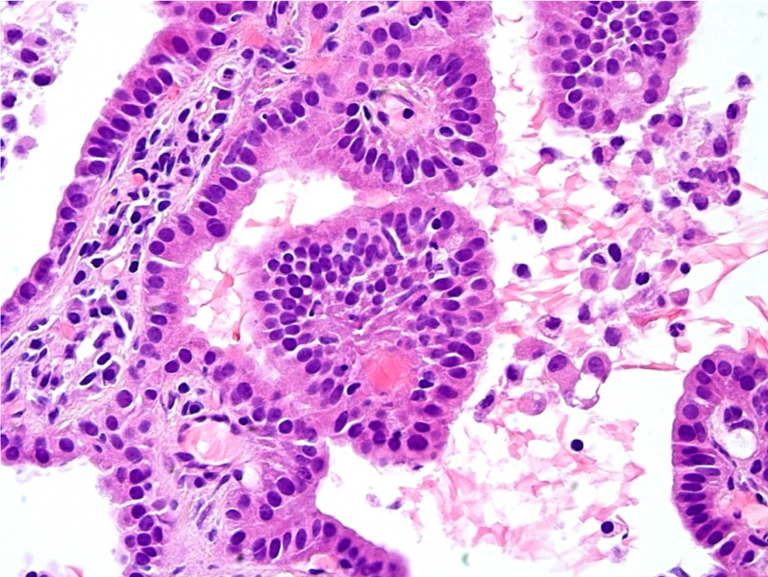

CT-guided biopsy of the lesion was again obtained. Histology results now showed papillary epithelial proliferation with papillary cores lined by cuboidal to low columnar nonciliated epithelial cells (Figure 3). There was absence of mitotic activity, and immunohistochemistry results were negative for chromogranin and synaptophysin, findings most consistent with papillary adenoma. The findings were morphologically distinct from her prior atypical carcinoid.

Figure 3. Histology results of the bilobed confluent nodule shows papillary profiles with well-formed papillary cores lined by cuboidal to low columnar nonciliated epithelial cells.